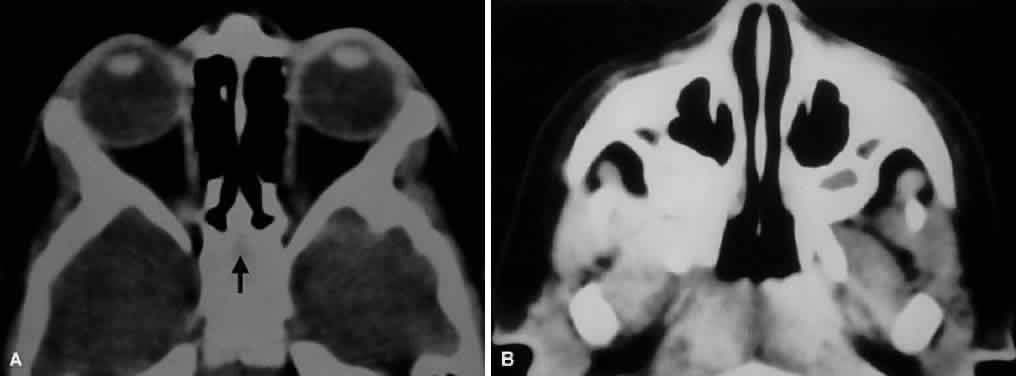

Fig. 9. An orbital lymphoma involving the skull base provides accentuation of the

apical spaces of the orbit. A. On this axial CT, the lesion infiltrates the CS, causing bulging and local

invasion of its lateral dural wall (small arrows). Invasion into the orbital apex through the superior orbital fissure (curved arrow) is seen. Note that the patient is slightly rotated in the scanner, because

the anterior clinoid and optic canal are visualized on the uninvolved

side. B. More inferiorly, the mass has invaded the pterygopalatine fossa (small arrows), located just posterior to the maxillary sinus. On the uninvolved side (large arrow), the fossa has areas of radiolucency, indicating the fat that normally

occupies this space. C. Axial MRI, T1-weighted image with gadolinium but without fat suppression. The

carotid siphon is seen within each CS as a flow void (arrowheads). Once again, note the inflamed lateral dural wall of the CS and local

invasion of the brain parenchyma (small arrows).D. Coronal T1-weighted MR image. The inferior rectus muscle is labeled with

a black arrow. The lymphoma has infiltrated the infraorbital canal (white arrow) within the orbital floor. E. Coronal MRI of the orbital apex shows infiltration from the CS to the

pterygopalatine fossa (PPF). Because there is no direct communication

between these spaces, the lesion must have spread through the superior

orbital fissure into the orbital apex, then through the inferior orbital

fissure. MT, middle turbinate. The lucency just above the CS is the

anterior clinoid process, with the optic nerve within its canal seen

as an opacity between the clinoid and the sphenoid sinus. F. Parasagittal MRI shows lymphomatous invasion of the pterygopalatine fossa

just behind the posterior wall of the maxillary sinus (small arrows). Note the thickening of the infiltrated infraorbital canal (large arrows) as it travels anteriorly to exit about 1 cm below the inferior orbital

rim. Fig. 9. An orbital lymphoma involving the skull base provides accentuation of the

apical spaces of the orbit. A. On this axial CT, the lesion infiltrates the CS, causing bulging and local

invasion of its lateral dural wall (small arrows). Invasion into the orbital apex through the superior orbital fissure (curved arrow) is seen. Note that the patient is slightly rotated in the scanner, because

the anterior clinoid and optic canal are visualized on the uninvolved

side. B. More inferiorly, the mass has invaded the pterygopalatine fossa (small arrows), located just posterior to the maxillary sinus. On the uninvolved side (large arrow), the fossa has areas of radiolucency, indicating the fat that normally

occupies this space. C. Axial MRI, T1-weighted image with gadolinium but without fat suppression. The

carotid siphon is seen within each CS as a flow void (arrowheads). Once again, note the inflamed lateral dural wall of the CS and local

invasion of the brain parenchyma (small arrows).D. Coronal T1-weighted MR image. The inferior rectus muscle is labeled with

a black arrow. The lymphoma has infiltrated the infraorbital canal (white arrow) within the orbital floor. E. Coronal MRI of the orbital apex shows infiltration from the CS to the

pterygopalatine fossa (PPF). Because there is no direct communication

between these spaces, the lesion must have spread through the superior

orbital fissure into the orbital apex, then through the inferior orbital

fissure. MT, middle turbinate. The lucency just above the CS is the

anterior clinoid process, with the optic nerve within its canal seen

as an opacity between the clinoid and the sphenoid sinus. F. Parasagittal MRI shows lymphomatous invasion of the pterygopalatine fossa

just behind the posterior wall of the maxillary sinus (small arrows). Note the thickening of the infiltrated infraorbital canal (large arrows) as it travels anteriorly to exit about 1 cm below the inferior orbital

rim.